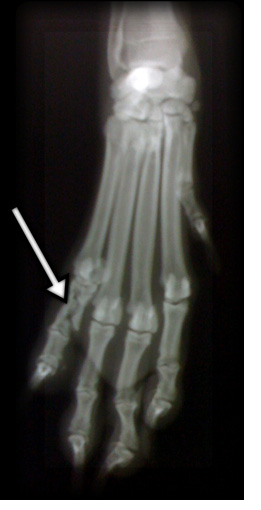

骨折を疑う部位を2方向からX線撮影を行い、状態を確認し判断します。

折れた骨が皮膚を破って目に見えるような重症の場合を解放骨折といい、幹部の細菌感染する機会が増えるので注意が必要です。

反対に骨折した部位が目に見えない皮膚の内部で起こっているものを閉鎖骨折といいます。